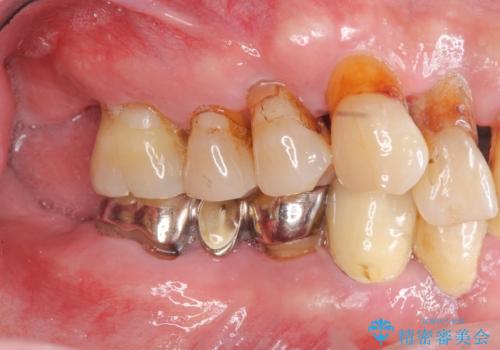

- 「歯がぐらぐらして噛めない、歯を抜いて欲しい、またしっかりと噛めるようになりたい。」、と歯周病治療を希望され来院されました。

歯の根本まで骨吸収が進み、ぐらぐらになってしまった歯を抜去し骨の造成を行ったのちインプラント治療を計画します。